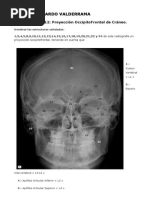

DIAGNOSTICO

 Cuando sospechan la existencia de

enanismo en un niño en desarrollo

(porque presenta un aspecto extraño,

un crecimiento anormal, o por el

aspecto de los huesos vistos en

radiografías), los médicos tratan de

averiguar la causa subyacente.